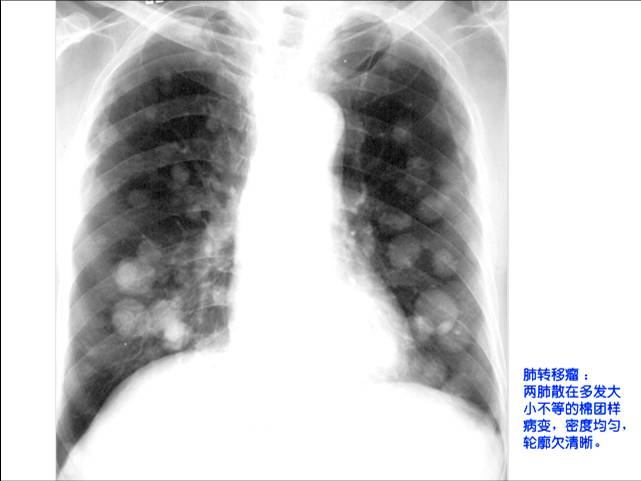

照片名称:肺转移瘤